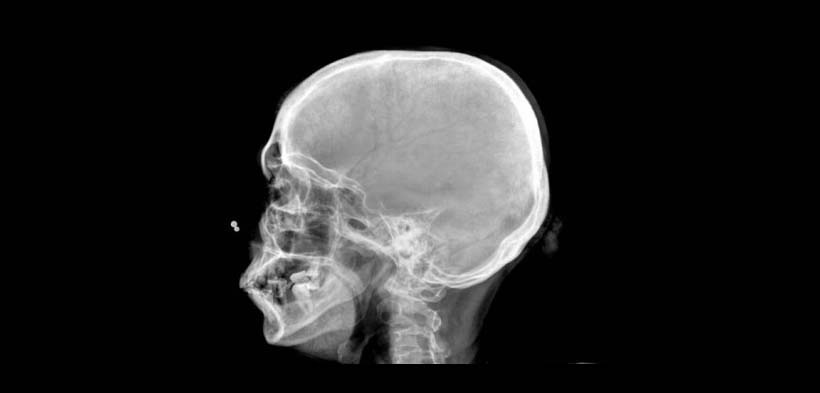

Fig. 2. Radiografía lateral de cráneo, que muestra una imagen radiopaca en la zona posterior de la bóveda craneal con aspecto de rayos de sol.